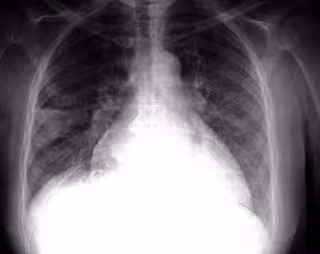

Pulmones, radiografía

Pulmones, radiografía - FLICKR/PULMONARY PATHOLOGY/CC BY-SA 2.0 - Archivo